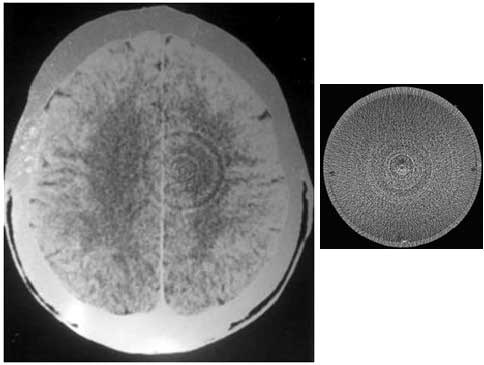

The Biostar-NLS device is a research device aimed at helping the professional or home user discover the true nature of disease. The true nature of disease can be observed in diffrent reigions of the brain.